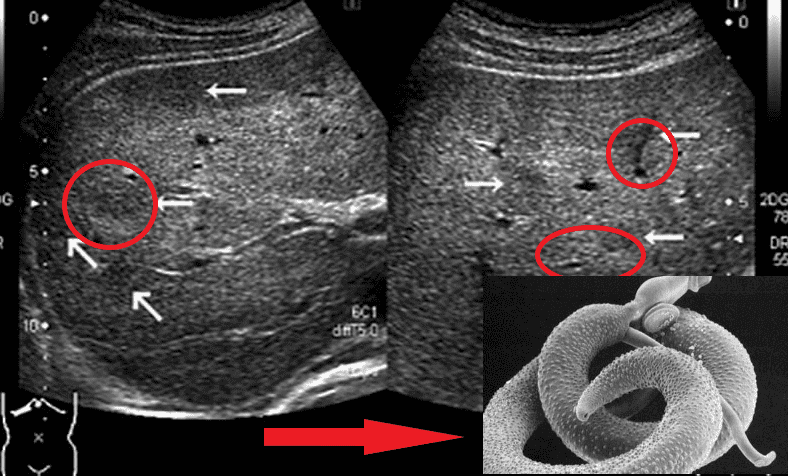

Представниками гельмінтів, що вражають життєво важливі органи, є Taenia solium, ехінокок (Echinococcus granulosus), трихінела (Trichinella spiralis). Ехінокок являє собою личинкову стадію гельмінта з роду Echinococcus. І це далеко не всі види паразитів, здатні убити людину.

Мозок, уражений паразитами